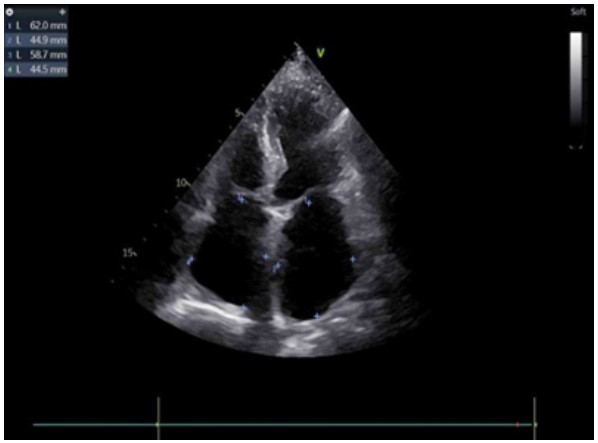

既往史:有高血压病史10年余,规律降压治疗,未监测血压。房颤病史2年余,2022年11月在本院超声心动图显示左心房见一不均质低回声团,位置随心动周期漂动(17 mm×16 mm)”(见图 1),左房前后径40 mm,左右径46 mm,上下径70 mm。LVEDD 39 mm,LVEF:60%。二尖瓣E峰0.92 m/s,最大压差3.39 mmHg(1 mmHg=0.133 kPa)。反流面积3.8 cm2,二尖瓣口频谱呈单峰。舒张期二尖瓣口前向血流,E < A,无舒张功能不全。进一步行经心脏超声造影提示:Flash后,左心室心腔内团块未见明显灌注(见图 2)。

| 注:左房内可见团块样回声影(箭头处),约17 mm × 16 mm 图 1 患者经胸腔超声心动图 |